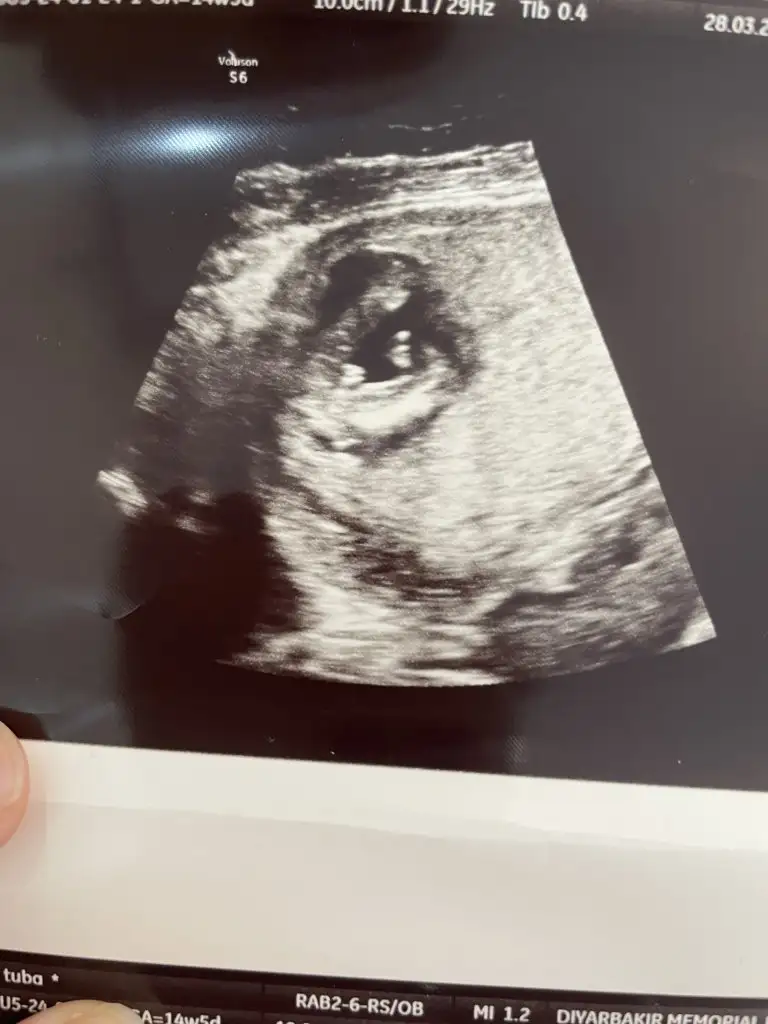

Oyyh ojbuldum canımtatlım hayırlı uğurlu olsun inş, erkek anaları olarak aramıza hoşgeldiniz diyelim :)) inşallah sorunsuz ilerlemeye devam ederiz ve sağlıkla bebeklerimizi kucağımıza alırız

Analarının kuzuları hepiciği

Bu sabah günaydın oğluşum diye selamlaştık, şimdiden keyfi bile alıyor aklımı